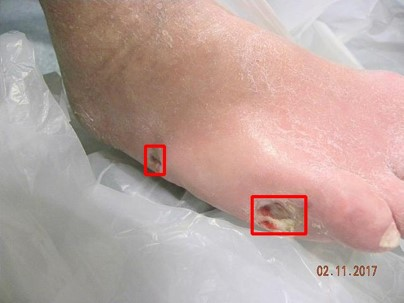

There has been a substantial amount of research on computer methods and technology for the detection and recognition of diabetic foot ulcers (DFUs), but there is a lack of systematic comparisons of state-of-the-art deep learning object detection frameworks applied to this problem. With recent development and data sharing performed as part of the DFU Challenge (DFUC2020) such a comparison becomes possible: DFUC2020 provided participants with a comprehensive dataset consisting of 2,000 images for training each method and 2,000 images for testing them. The following deep learning-based algorithms are compared in this paper: Faster R-CNN, three variants of Faster R-CNN and an ensemble method; YOLOv3; YOLOv5; EfficientDet; and a new Cascade Attention Network. For each deep learning method, we provide a detailed description of model architecture, parameter settings for training and additional stages including pre-processing, data augmentation and post-processing. We provide a comprehensive evaluation for each method. All the methods required a data augmentation stage to increase the number of images available for training and a post-processing stage to remove false positives. The best performance is obtained Deformable Convolution, a variant of Faster R-CNN, with a mAP of 0.6940 and an F1-Score of 0.7434. Finally, we demonstrate that the ensemble method based on different deep learning methods can enhanced the F1-Score but not the mAP. Our results show that state-of-the-art deep learning methods can detect DFU with some accuracy, but there are many challenges ahead before they can be implemented in real world settings.